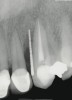

A 51-year-old man presented with a 12-mm probing depth on the mesiobuccal and distalbuccal surfaces secondary to a root fracture extending to the apex of the maxillary left canine (Figure 14 ). The tooth was extracted without flap elevation, and the socket and periradicular defect were thoroughly degranulated using magnification and fiber optic illumination. The socket and bony defect were grafted with an FDBA wetted with rhPDGF-BB (10 minutes). A resorbable collagen membrane was cut, adapted, and stabilized with cyanoacrylate over the extraction socket, as in the Bio-Col technique.44 Healing proceeded uneventfully with clinical closure and epithelialization of the extraction site after 21 days. At 5 months post-treatment, the radiographic findings were consistent with complete bone fill of the defect (Figure 15 ). The osteotomy for implant placement was prepared with a trephine bur. The core specimen was submitted for histologic evaluation; the findings revealed areas of intense osteogenesis with new bone trabeculae surrounding and interconnecting the graft particles (Figure 16 ). Histologic evidence showed new bone repopulating regions of graft particles (Figure 17).

Figure 14  Periapical radiograph of fractured maxillary left canine with a calibrated point (15-mm markings) demonstrating extent of attachment loss on mesiobuccal aspect of the tooth. Similar probing was present on the distobuccal aspect of the tooth.

Figure 14